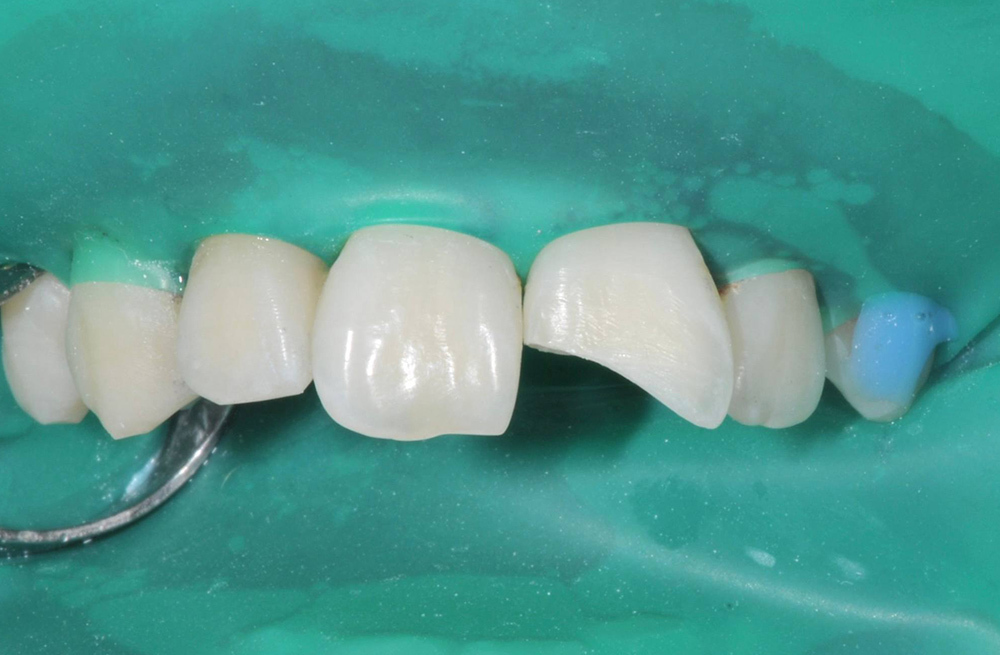

Устранение застревания пищи между зубами путём замены старых несостоятельных пломб